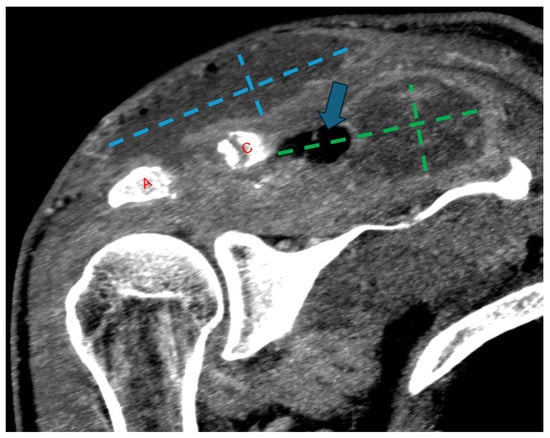

Figure 4.

Follow-up coronal computed tomography (CT) image post-contrast at the level of the AC joint (red A = acromion; red C = clavicle). Multilocular peripherally enhancing and gas-containing (blue arrow) collections have redeveloped in the superficial subcutaneous tissue directly above the AC joint (blue dashed lines) and in the supraspinatus fossa (green dashed lines). Progressive widening of the AC joint can be related to interval debridement versus progressive osteomyelitis.